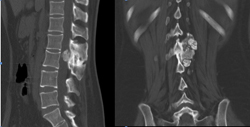

下面这个病人是个25岁的青年男性,因为下肢无力在当地医院就诊,发现T12肿瘤压迫脊髓。为了挽救神经功能,当地医生给病人做了后路椎板切除减压,椎体内肿瘤刮除及椎弓根螺钉固定手术。术后肿瘤的病理结果回报为骨巨细胞瘤。虽然神经功能改善明显,步行出院,但1年半之后肿瘤复发,不仅再次压迫脊髓而且肿瘤蔓延到相邻的3节脊椎。

图1-1,男性,25岁,术前MRI显示T12椎体、附件及椎旁肿瘤,累及椎管压迫脊髓。

图1-2,术后X片显示当地医院行后路T12附件切除减压,经椎弓根椎体肿瘤切除,T11-L1椎体间异体骨块支撑,T10,11-L1,2椎弓根螺钉固定术。

图1-3,术后1年半CT显示肿瘤复发,累及T11-L1椎体,左侧椎旁肿瘤累及腰大肌从T11蔓延到L2-3椎间盘水平。

图1-4,术后1年半MRI显示肿瘤复发,而且再次侵及椎管造成脊髓压迫。